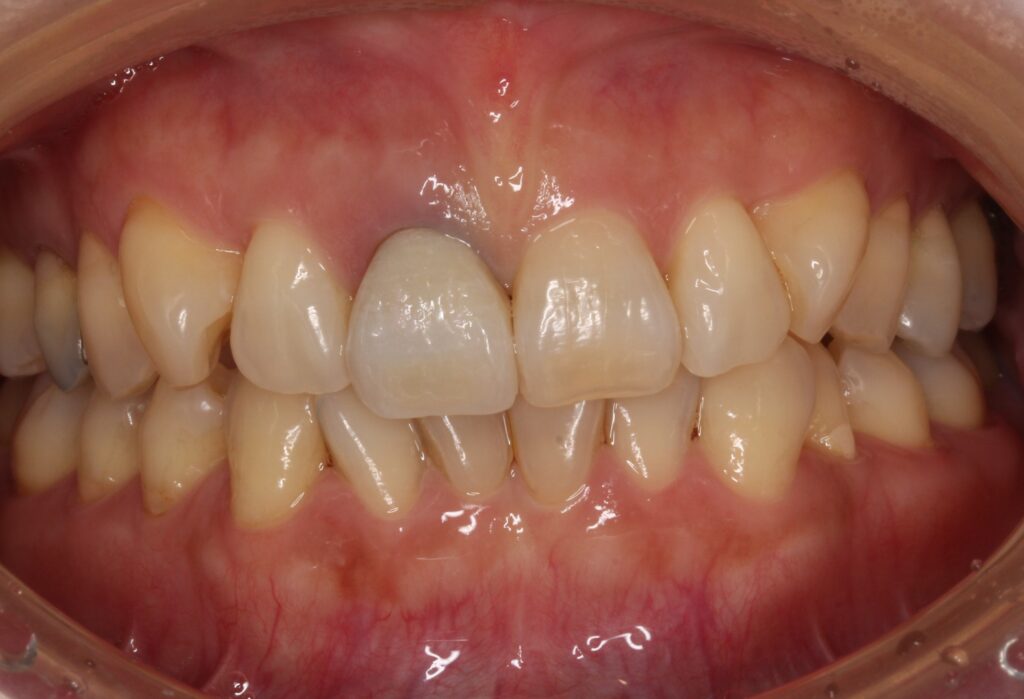

お口の中の状態を見てみましょう。

よくみると左側の前歯が不自然な感じで、歯の根元が暗く見えます。

矢印の歯ですね。

以前の治療で歯の神経を取り、かぶせ物をしたとの事です。

歯の根元が黒くなっています。